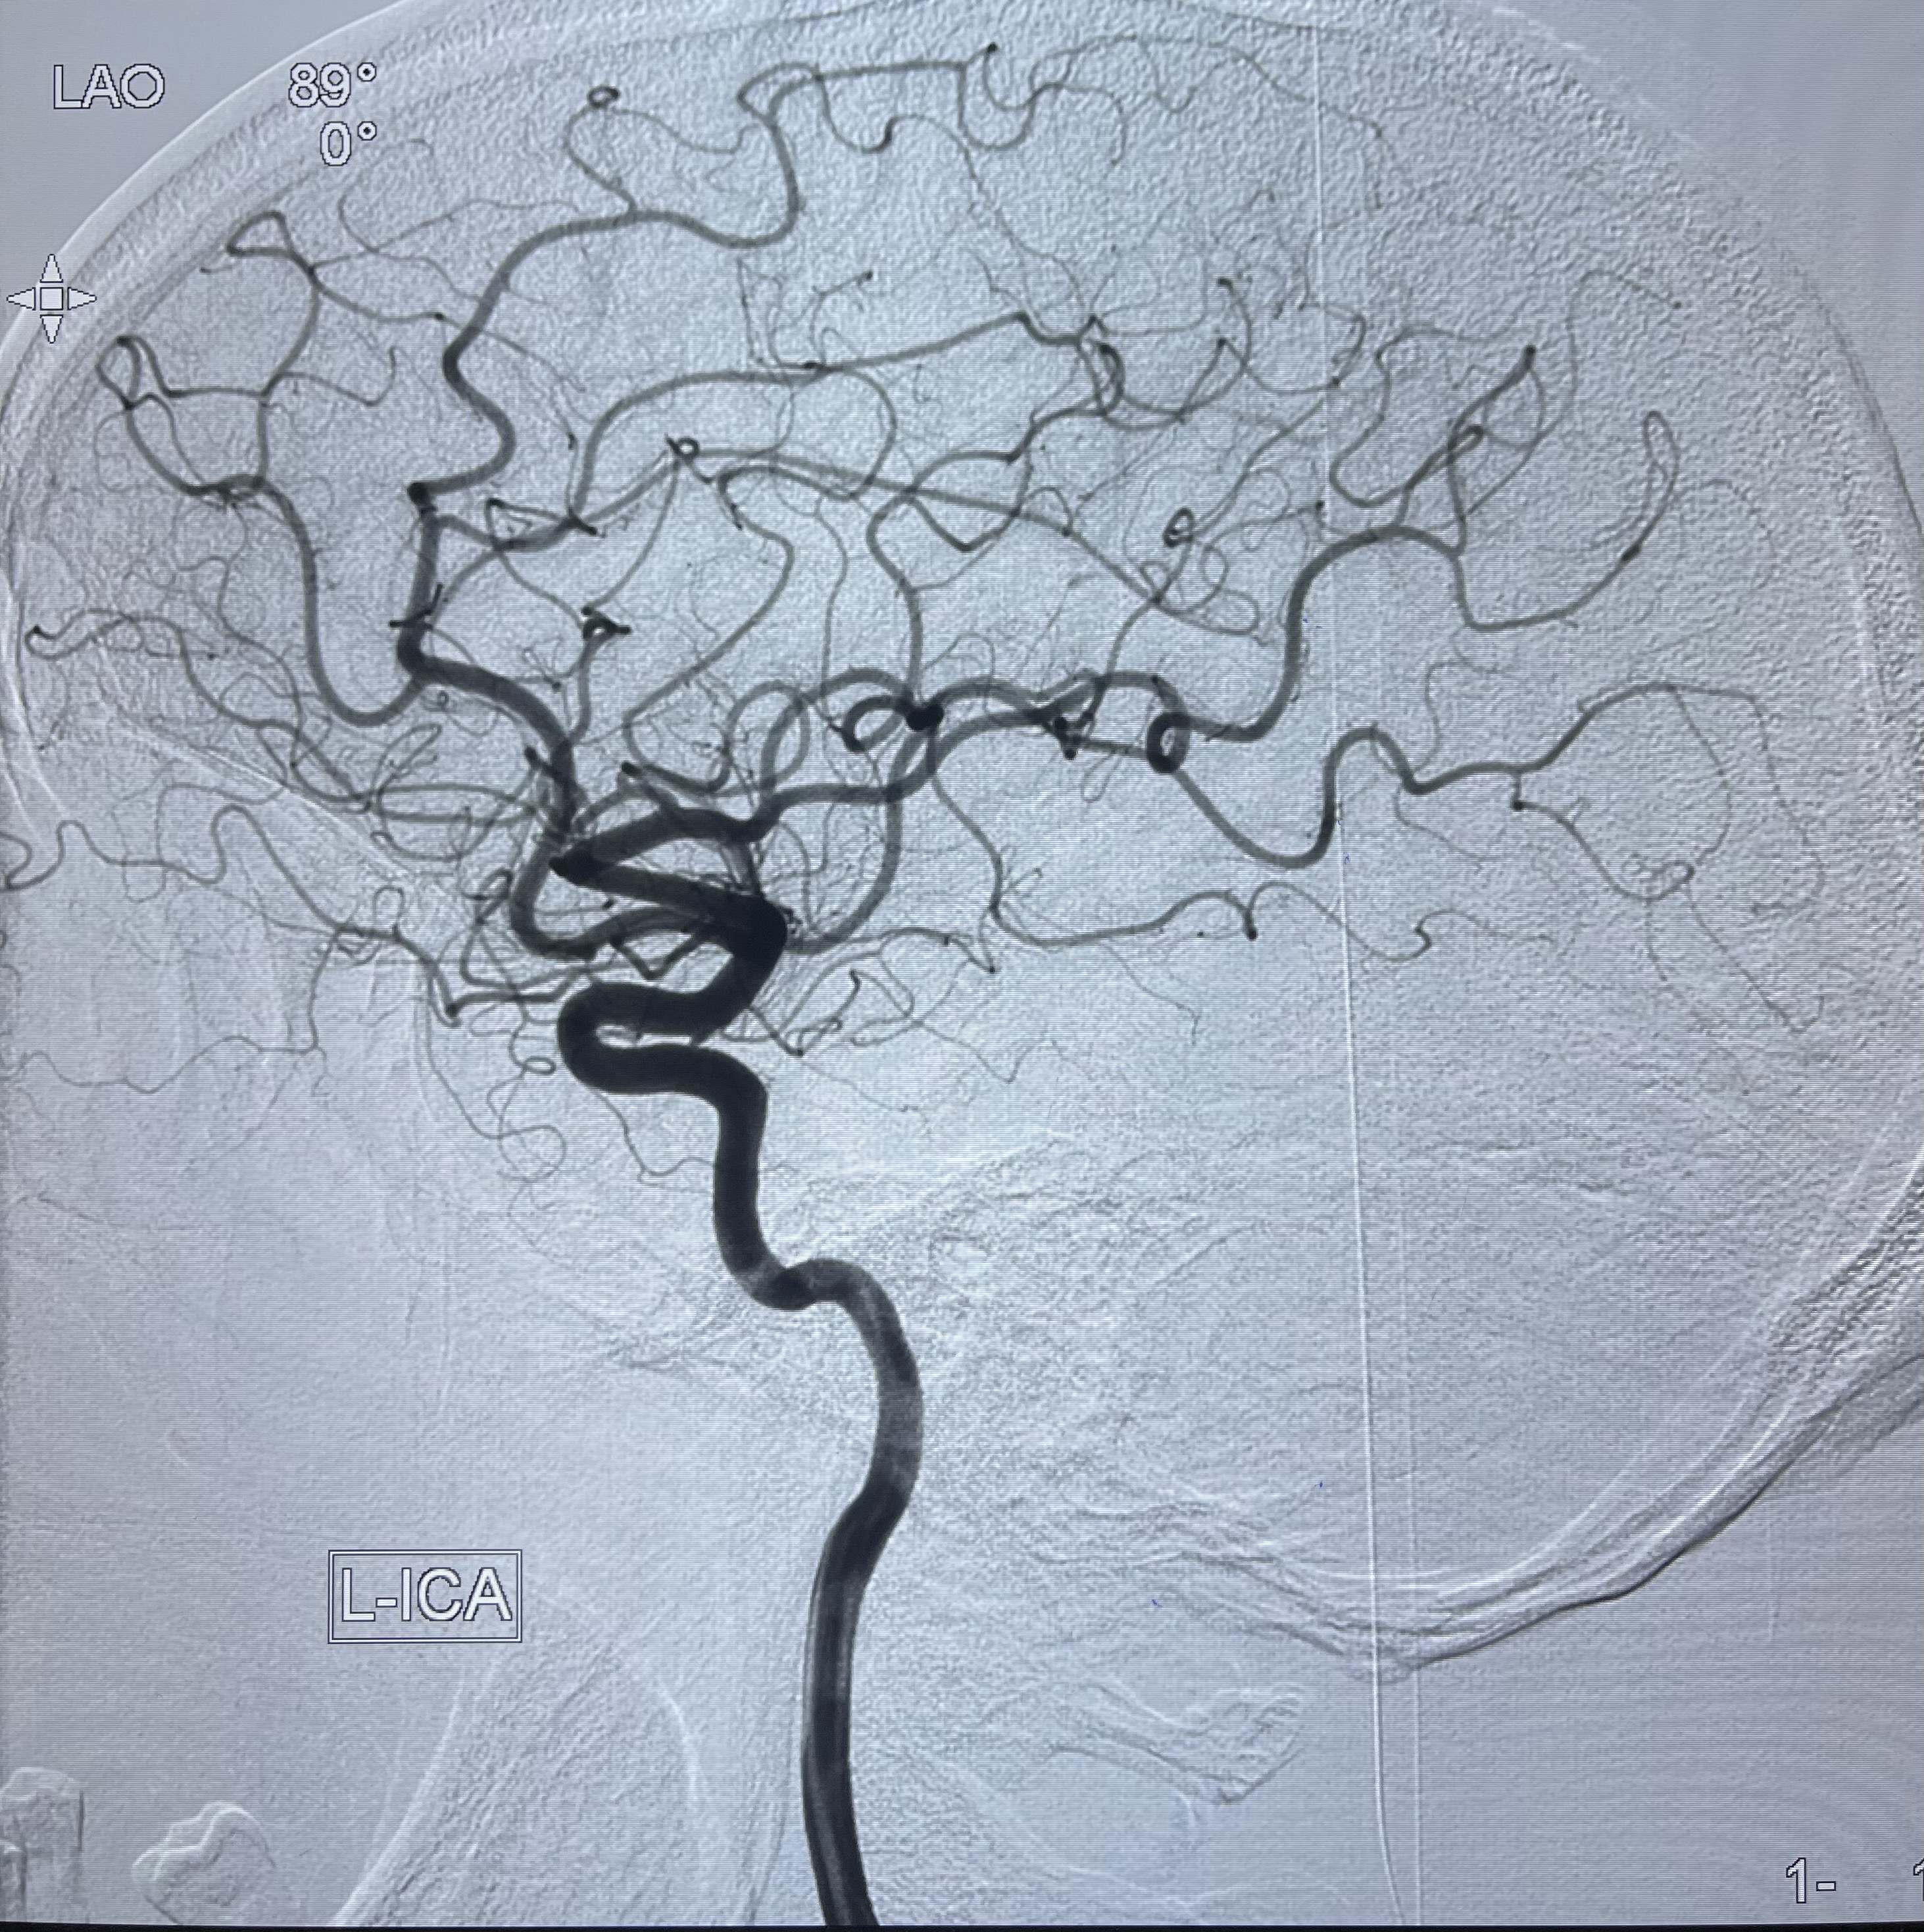

2021-03-08行全脑血管造影

治疗策略:

1.左侧椎动脉夹层动脉瘤密网支架辅助栓塞:

1.右侧颈内动脉夹层动脉瘤Lvis支架辅助;